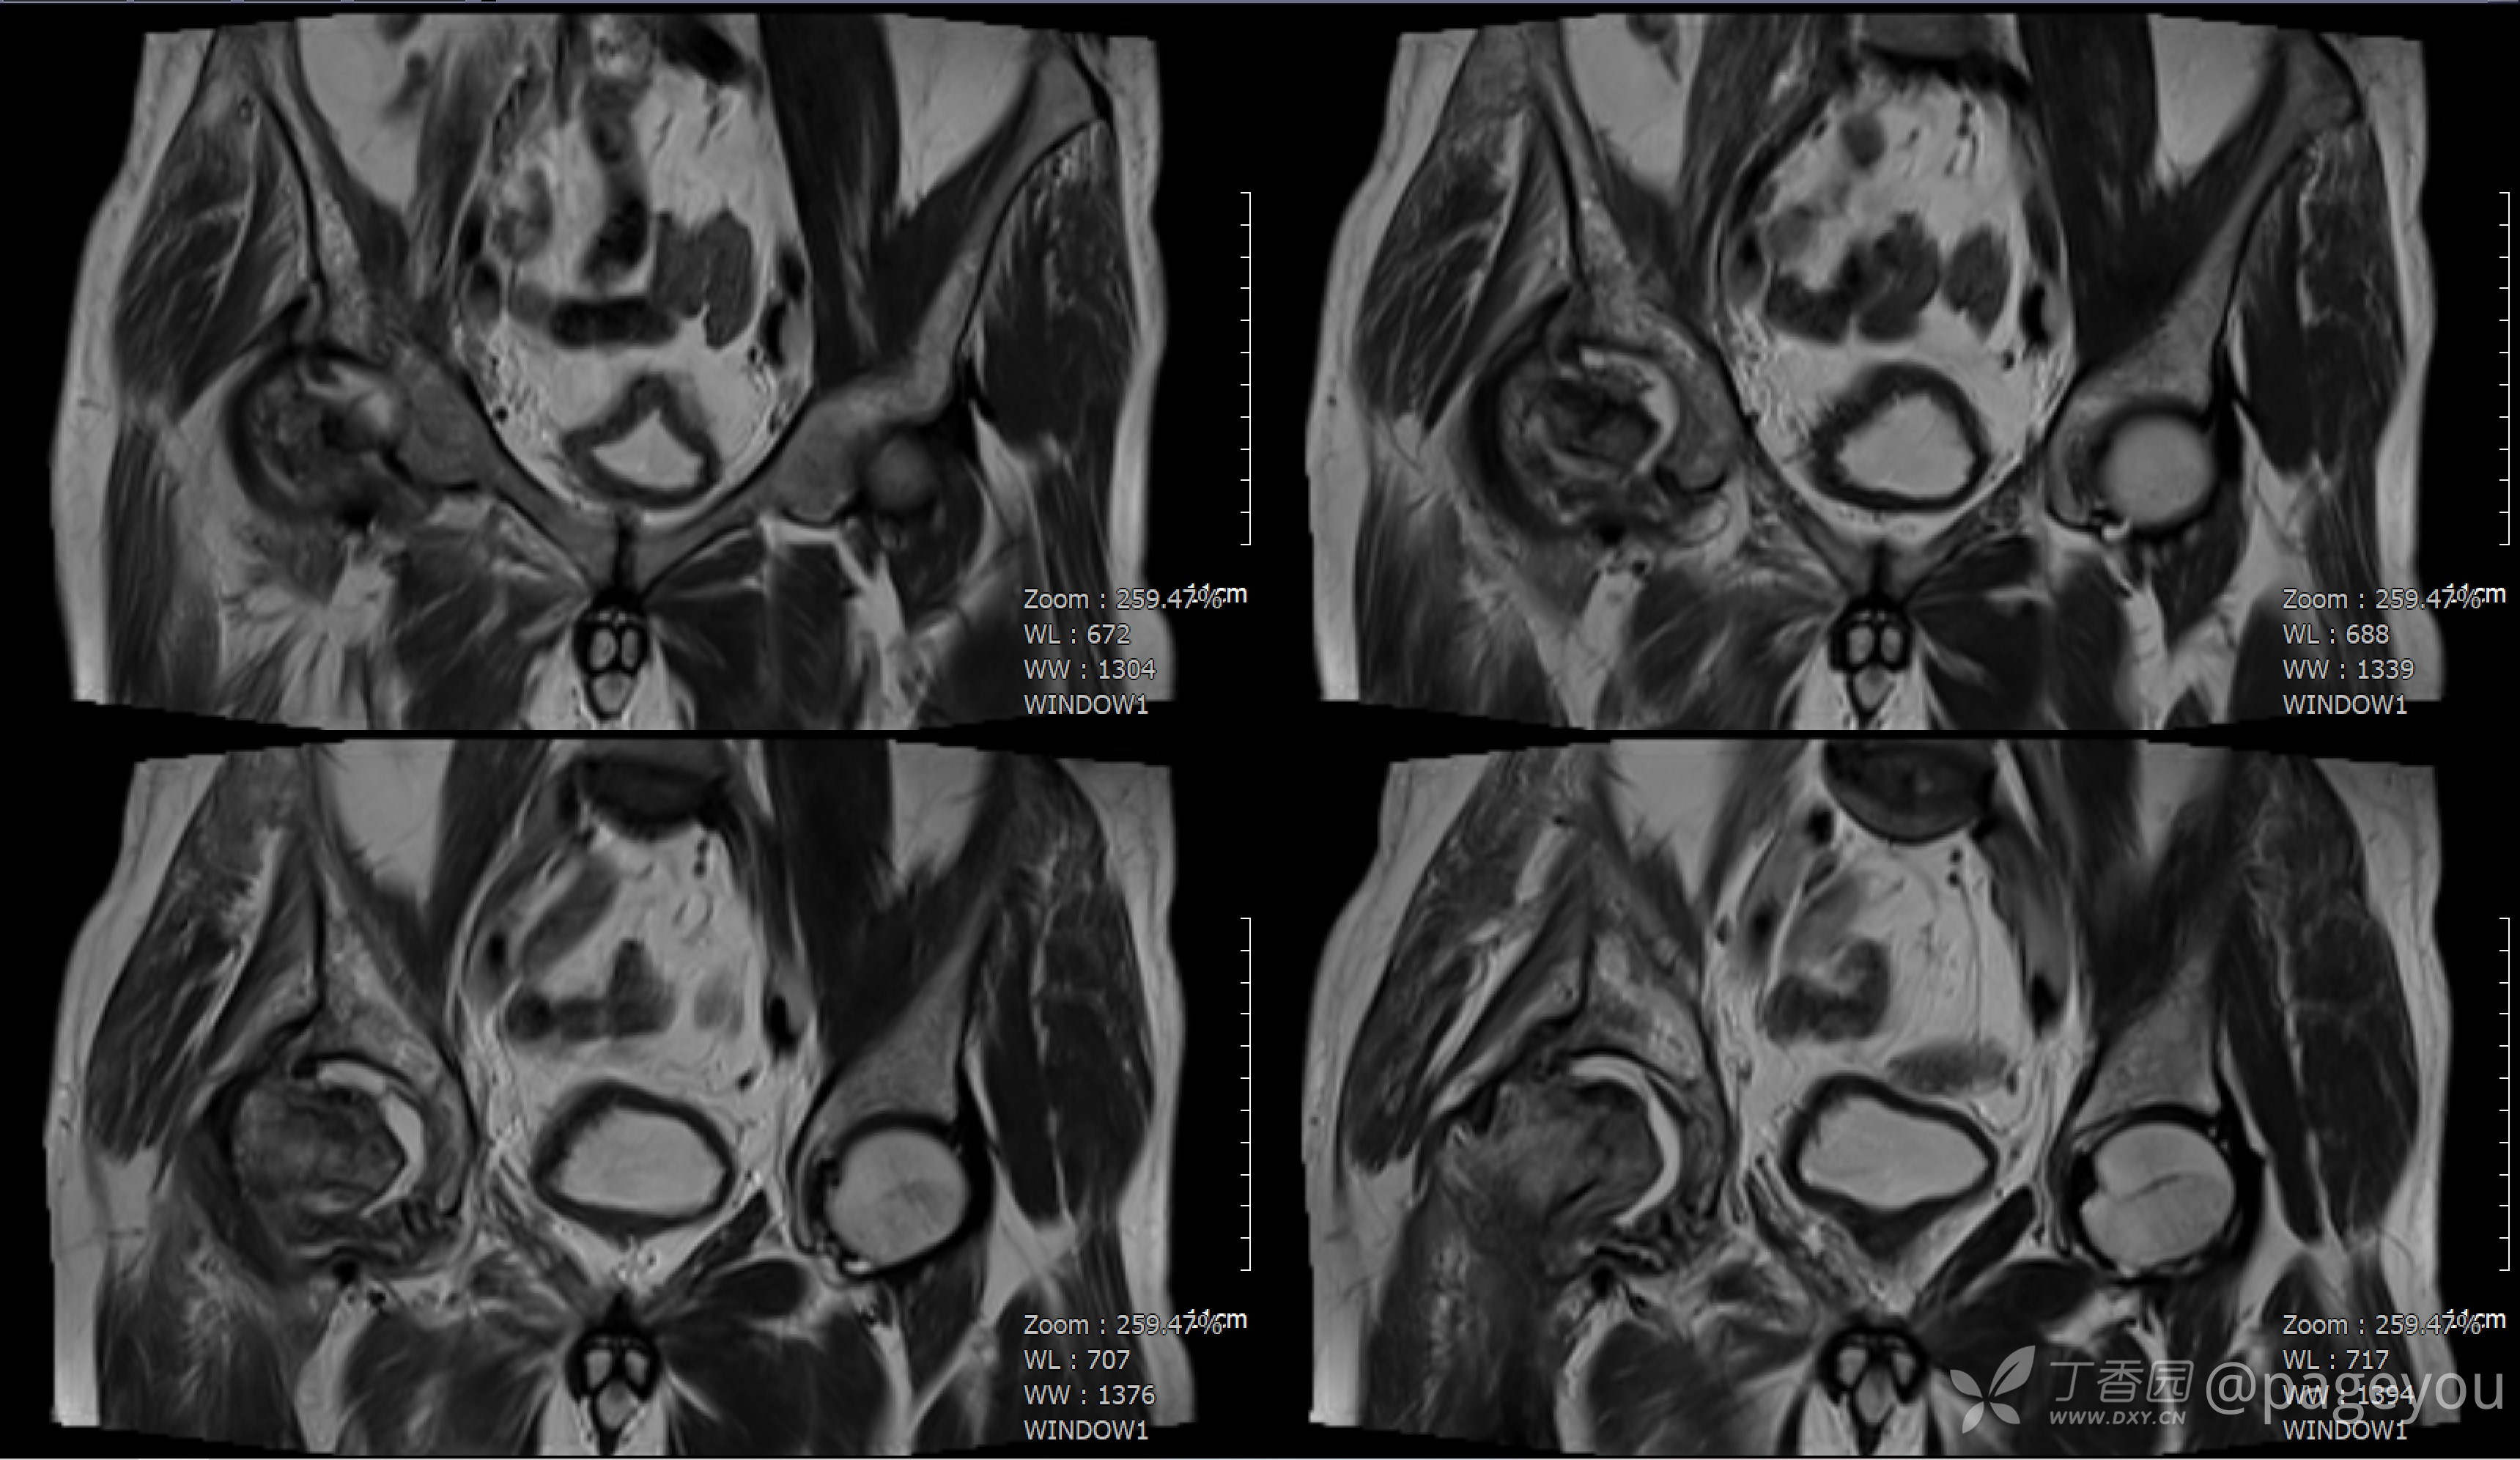

查骨盆MRI: